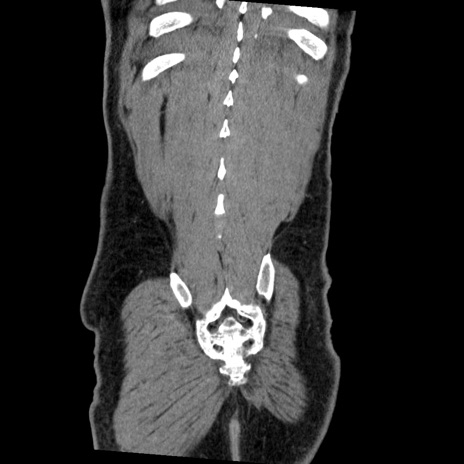

横断像

【症例】50歳代男性

【主訴】腹痛

【現病歴】AVMからの被殻出血のため回復期リハ病棟入院中。 本日午後3時頃急に下腹部痛が出現した。

【既往歴】AVM、被殻出血、虫垂炎、高血圧

【身体所見】意識晴明、左半身不全麻痺、会話の理解は良好、36.5°C、腹部:膨隆、全体に板状硬、下腹部正中に圧痛点あり、反跳痛-、筋性防御不明、右下腹部にope scar

【データ】WBC 9400、CRP 0.06